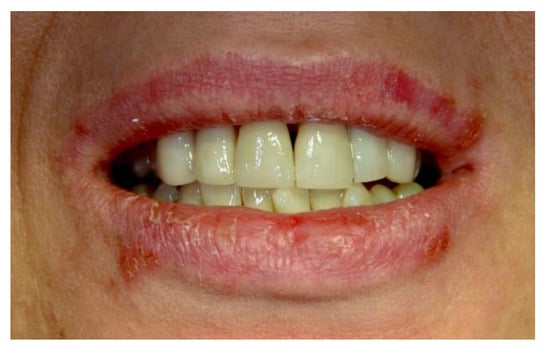

Figure 1, Figure 2, Figure 3, Figure 4, Figure 5 and Figure 6 show examples of conditions of the oral mucosa in the study groups.

Figure 4. Recurrent herpes labialis.

Ijerph 20 00835 g004